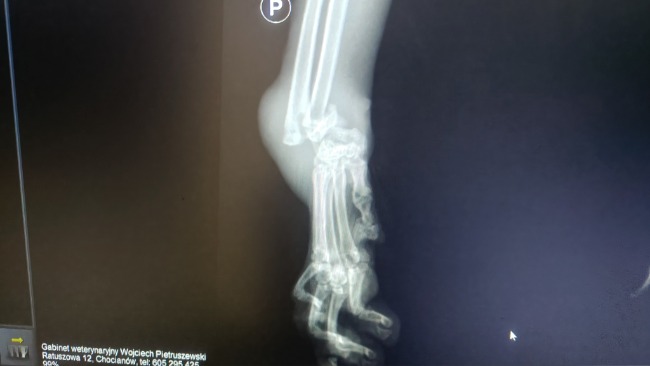

RTG w lecznicy odebrało nam dech.

Ale dramat, który rozgrywa się w ciele tego maleństwa, widać aż za dobrze na jednym obrazie.

Zwichnięcie nadgarstka.

Kości przemieszczone.

Wykręcone wokół własnej osi.